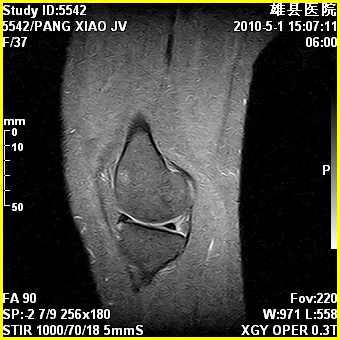

标题: MRI2894:患者右膝关节疼痛两月余,无明显外伤史 [打印本页]

标题: MRI2894:患者右膝关节疼痛两月余,无明显外伤史

右股骨下端前内侧类圆形异常信号,位于干骺端,呈长t1长t2改变,但信号不均,t1图上病灶中心见小片状稍高信号影,t2图上见散在稍低信号影,stir像呈高信号,因病灶较小,缺乏特征性改变,结合患者年龄及部位,考虑嗜酸性肉芽肿可能性大。胫骨关节面下的小囊状异常信号,如果一元论考虑则为嗜酸性肉芽肿,不过发生在这个部位的少见,二元论考虑为邻关节骨囊肿。半月板与前后交叉韧带均未见异常。

临关节骨囊肿可优先考虑